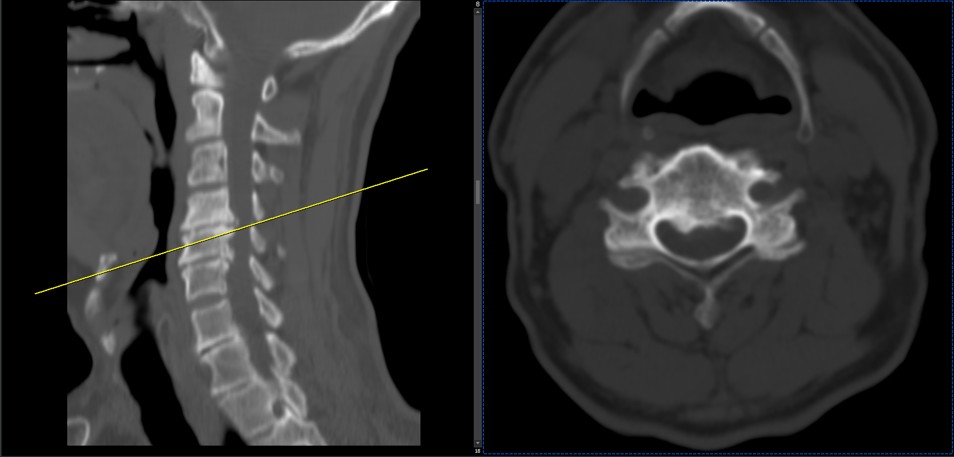

41 years old man presented to my clinic in October 2023 with acute and sever R neck pain with radicular pain to his R upper extremity along C6 dematom since 2 weeks ago. Examination didn’t show any upper motor signs. Was suggested urgent surgery

I ordered EMG/ NCV : showed mild R C6, C7 irritation without any active axonal loss

In his MRI was reported R. para R. IVF Massive extrusion. I decided to control his pain and manage this patient with reevaluation of patient every other session. For 5 sessions i just used acupuncture and laser and IFC and mild adjustments to his R. T3-T7 and mild arthosteem to above and below involved segment. Cervical adjustment considered contraindicated for this patient. From session 6th- 8th i started to use mild/gentle cervical decompression. He used soft cervical collar all the time. His pain decreased by 80 percent

I gave him cervical traction pump to be used 3-5 times per day at home for the next 3 months and i released the patient. He was evaluated every week once for one month and after that every 2 weeks. After 3 month I repeated MRI. Size of the herniated disc was reduced greater than 50 percent. Asked him to do another mri in 6 months

In general: Precise selection of the patients, examination,diagnosis, plan of management, reevaluation and treatment can be done by doctors of chiropractic for the patients with spinal disc herniation and stenosis Moreover giving reasonable time to these kind of patients under direct supervision by their chiropractic doctors can prevent unnecessary surgery. Proper selection of these kind of patients is another important fact that can be done precisely by chiropractors.

MRIs before and after proper management of this patient: